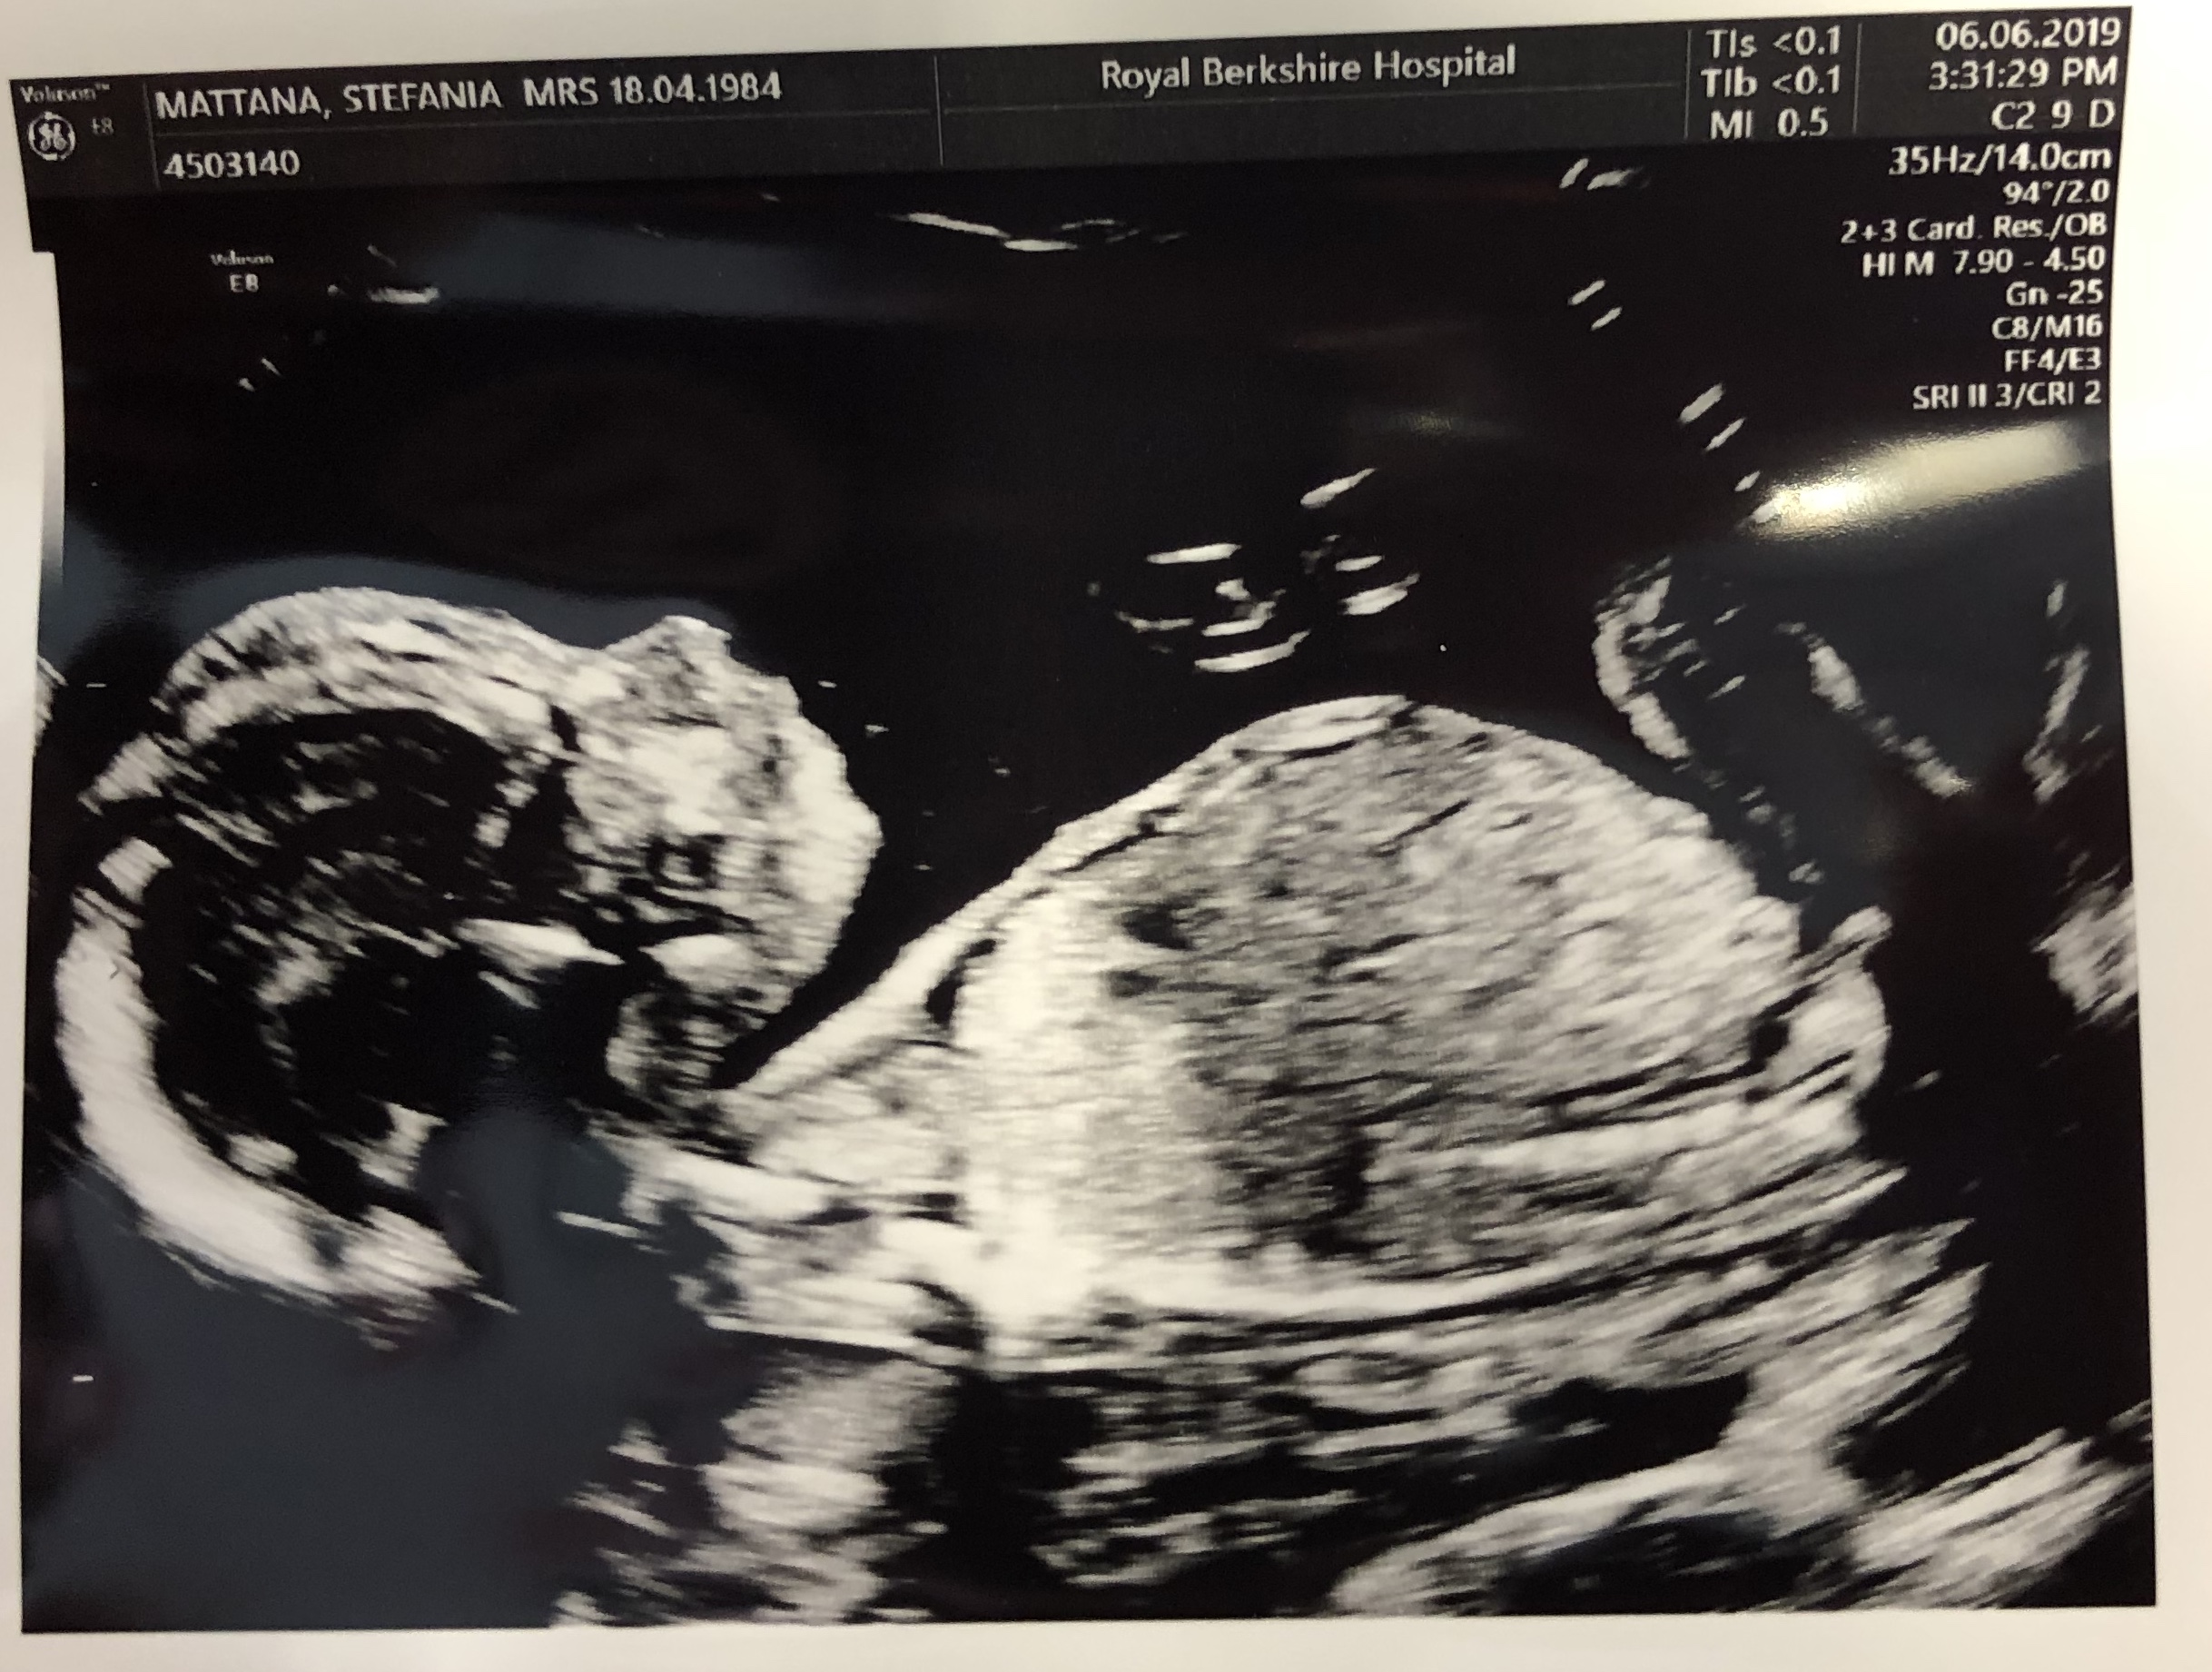

I know you want to see the latest Frosty’s pics, so here they are!

Frosty has grown SO MUCH since week 12 when we had the latest scan!

My sister made us notice that in one picture it seems like there’s a duck in my womb along with Frosty. Franz has his theory about that: